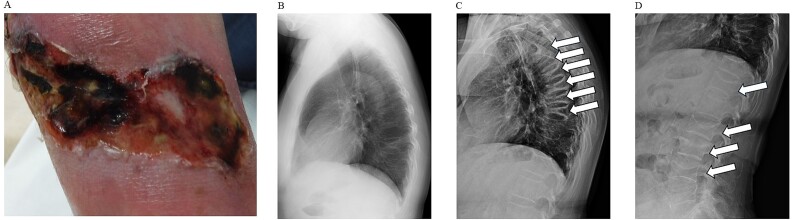

钙化反应,又称钙化性尿毒症小动脉病(CUA),是一种罕见的疾病,有许多未知的治疗和诊断方面。其特点是小血管钙化和血栓形成。这种疾病导致进行性皮肤钙化、坏死性溃疡和感染,并伴有高死亡率。虽然主要受影响的部位往往在皮肤上,但影响骨骼的部位也很重要。我们报告一个合并快速进展的多椎体骨折和严重骨质疏松症的病例。患者住院后5个月内连续发生5次椎体骨折,血液检查显示骨吸收标志物骨型抗酒石酸酸性磷酸酶(TRACP-5b)水平异常高。因此,静脉注射硫代硫酸钠和高压氧治疗用于治疗钙化反应引起的皮肤病变,并开始支架治疗和地诺单抗治疗椎体骨折。该入路迅速降低了TRACP-5b水平并阻止了椎体骨折链。我们的结论是,为了维持CUA患者的生活质量,早期治疗原发性皮肤病变和合并症是必不可少的。

Calciphylaxis, also known as calcific uremic arteriolopathy (CUA), is a rare disorder with many unknown treatment and diagnostic aspects. It is characterized by calcification and thrombosis of small blood vessels. This disease leads to progressive skin calcification, necrotizing ulcers, and infections and is associated with a high mortality rate. Although primarily affected sites tend to be on skin, those affecting bones are also significant. We report a case of CUA complicated with rapidly progressing multiple vertebral fractures and severe osteoporosis. The patient experienced a series of five vertebral fractures within 5 months after hospitalization, and blood tests revealed abnormally high levels of bone resorption marker bone-type tartrate-resistant acid phosphatase (TRACP-5b). Consequently, intravenous sodium thiosulfate and hyperbaric oxygen therapy were administered for the treatment of skin lesions caused by calciphylaxis, and brace therapy and denosumab treatment were initiated for vertebral fractures. This approach rapidly decreased TRACP-5b levels and arrested the chain of vertebral fractures. We concluded that to maintain the quality of life of patients with CUA, early treatment of primary skin lesions as well as comorbid conditions is essential.